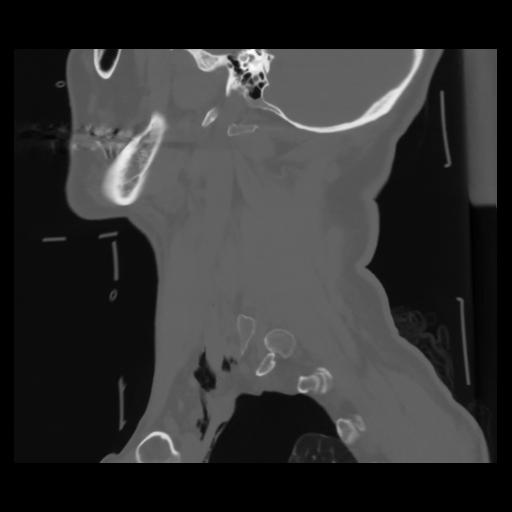

14 P.BLANDAS,,Sagittal,2.000,P.BLANDAS,Sagittal,